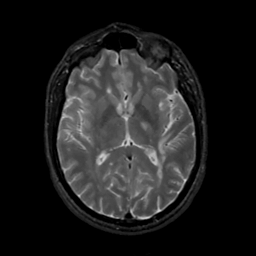

MR Study #3, February 24, 1991 -- Slice #26